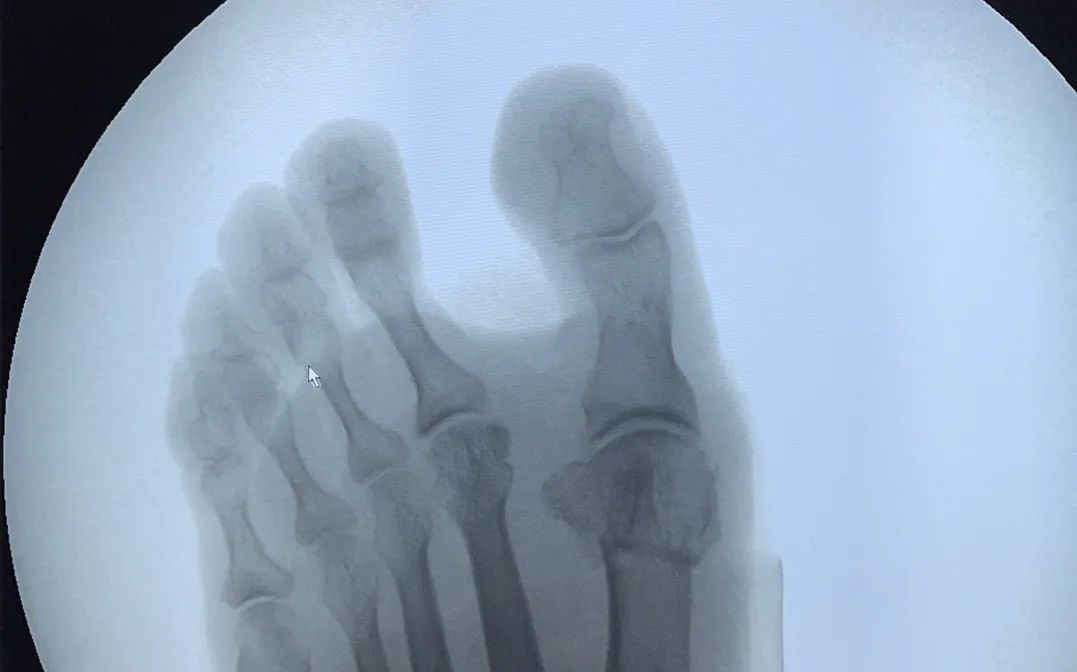

△患者手術(shù)前后比對(duì)

微創(chuàng)矯形干預(yù)拇指外翻的優(yōu)勢(shì)

? 術(shù)后創(chuàng)口僅0.5-1cm

? 手術(shù)時(shí)間雙腳僅需30-40分鐘

? 術(shù)后即可穿戴矯正器

? 6小時(shí)候后可下地行走

? 6周后可正常穿鞋生活